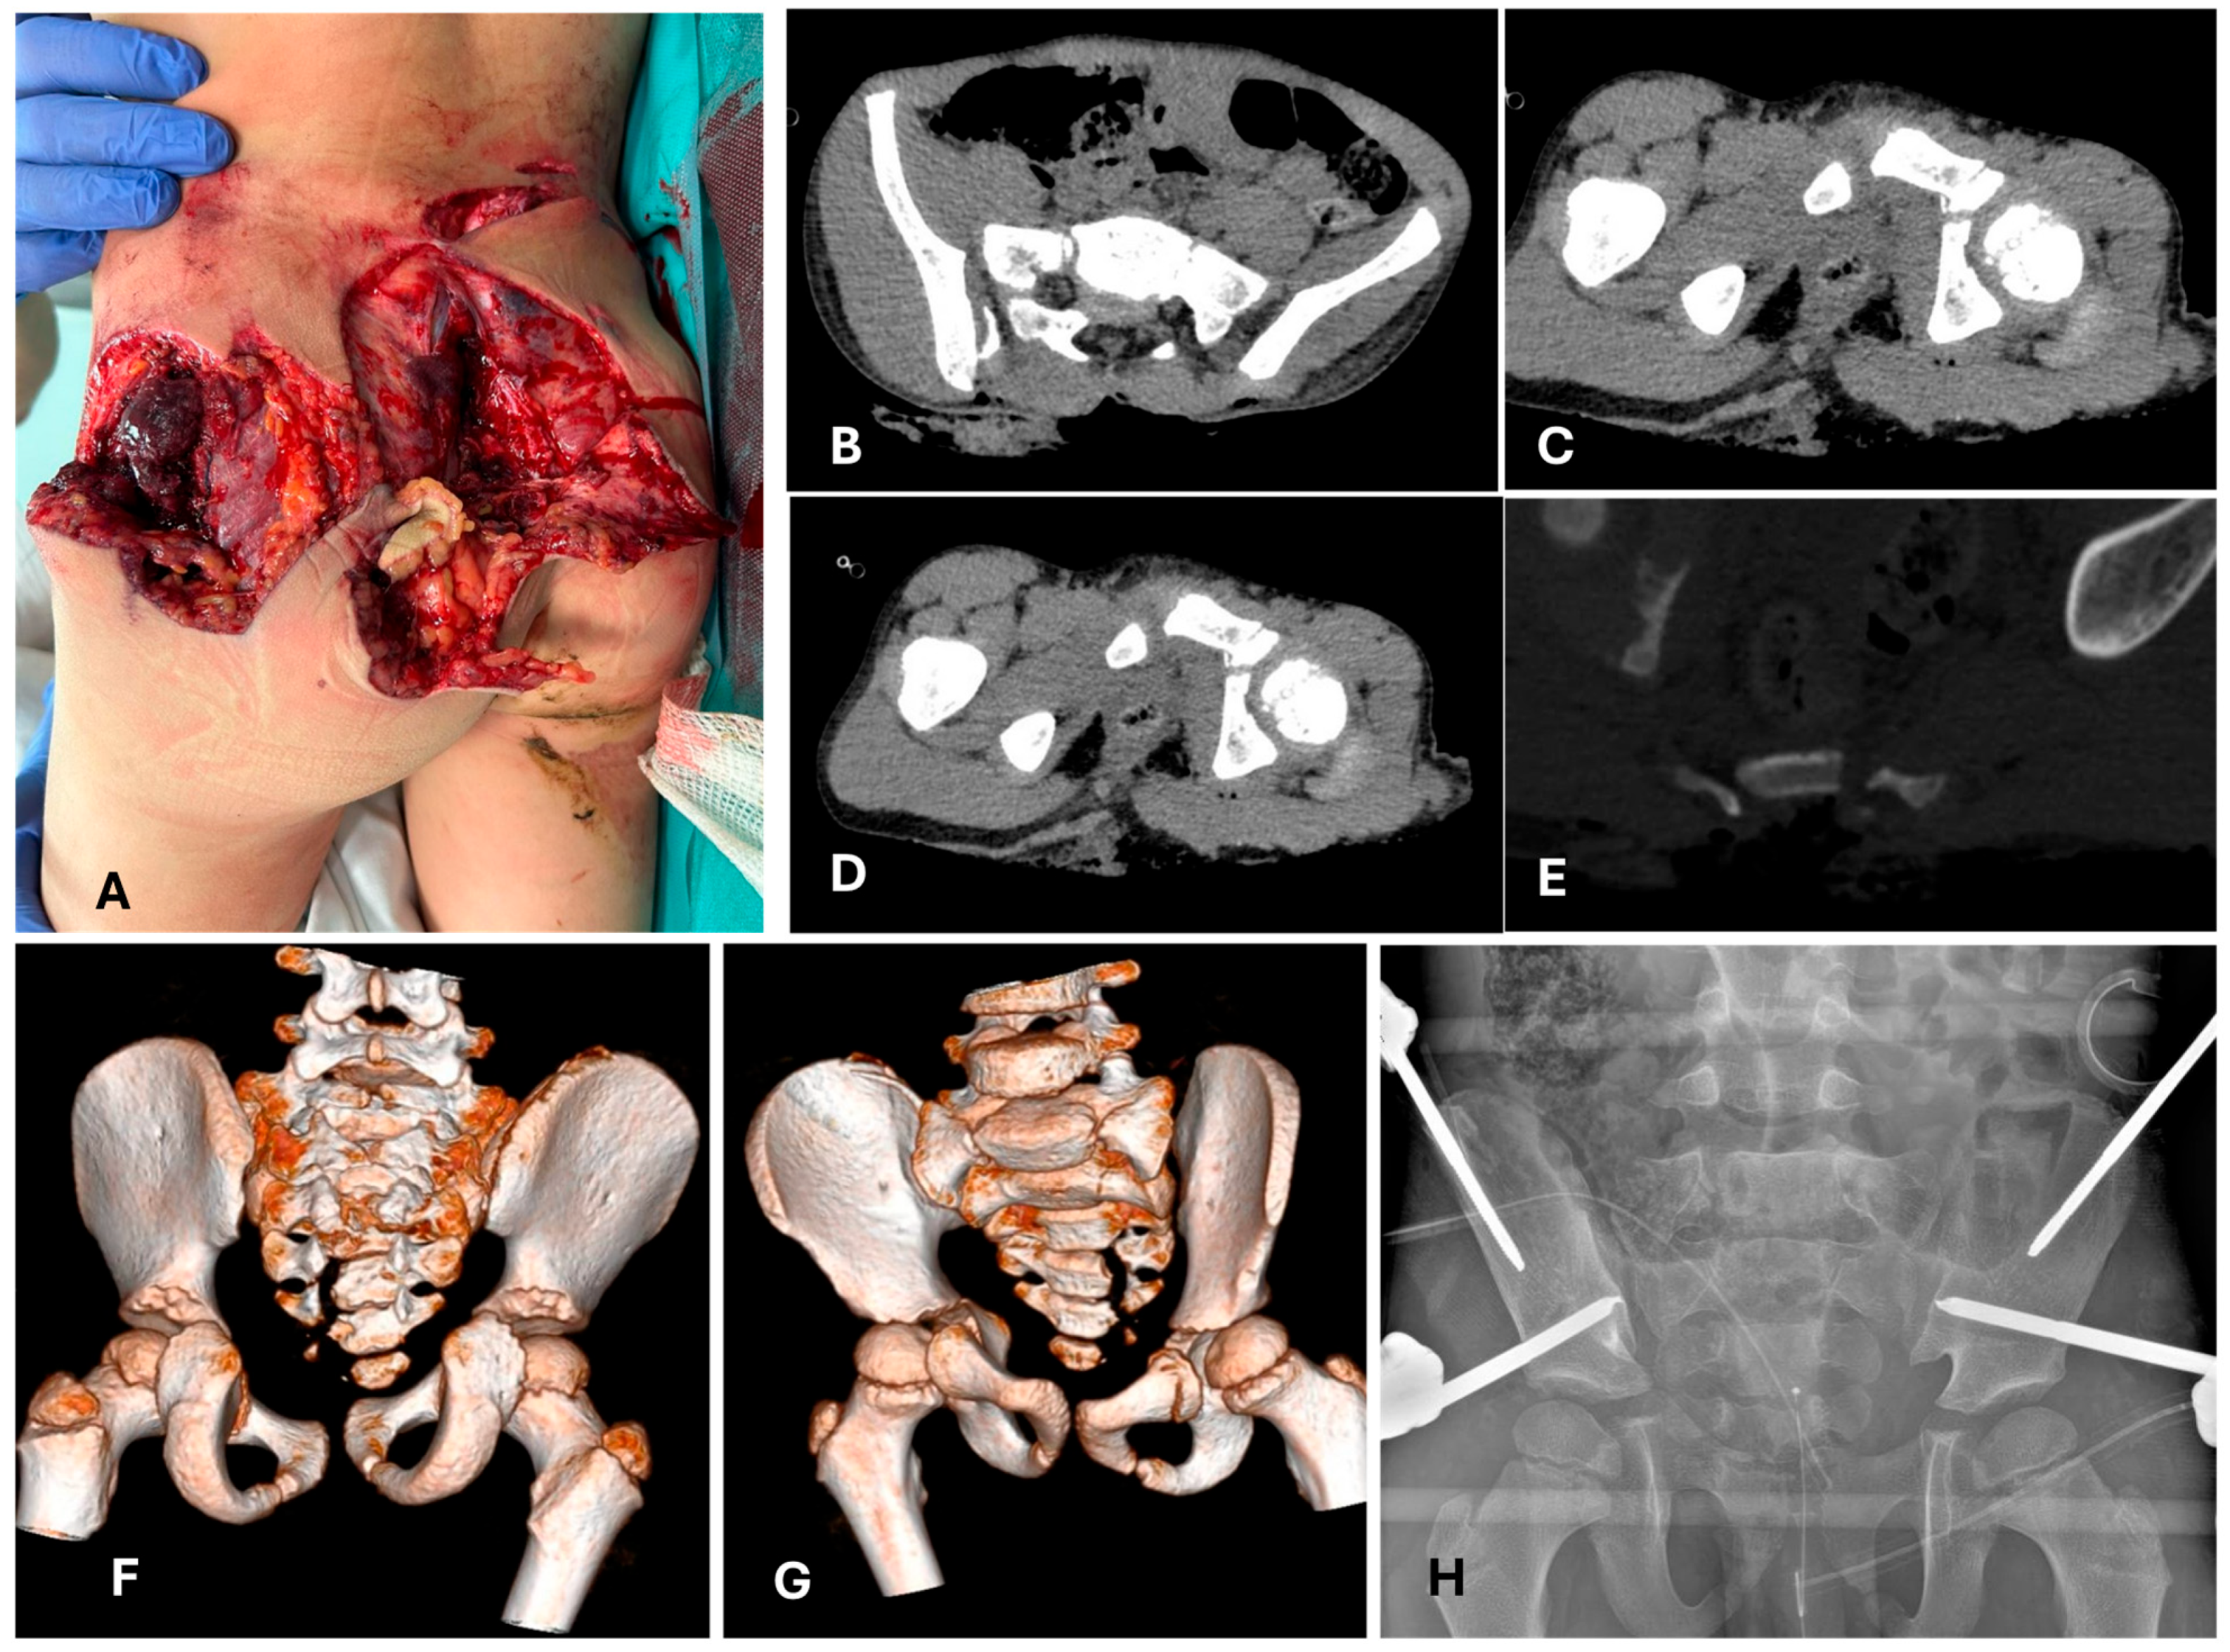

- In the age-group 15–17 years, 23/23 (100%) cases were treated with temporary external fixation (ExFix);

- In the age group 12–14 years, 9/14 (64%) cases were treated with ExFix, and 5/14 (26%) cases were treated with elastic stable intramedullary nails (ESIN);

- In the age group 5–11 years, 1/5 (20%) cases were treated with ExFix, and 4 cases were treated with ESIN;

- In the age group 0–4 years, 2/4 (50%) cases were treated with ESIN, and 2/4 (50%) cases were treated with a hip spica cast.